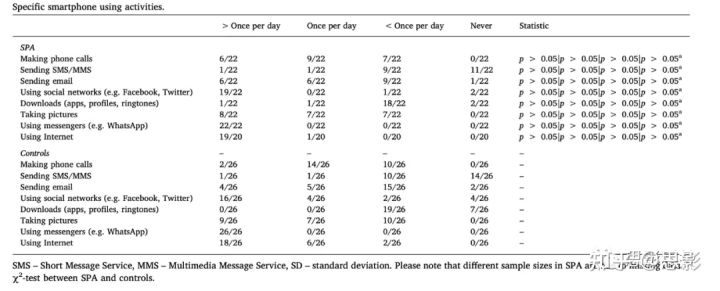

表2:具体的智能手机使用

SMS -短消息服务,MMS -多媒体消息服务,SD -标准偏差。请注意SPA中不同的样本量是由于缺少数据造成的。a:SPA与对照组之间的χ2检验。

SPA患者和对照组在年龄、性别和教育年限方面没有显著差异。正如预期的那样,SPA患者花在智能手机上的时间明显更多,就SPAI总分而言,组间存在显著差异。各组间BDI(Beck抑郁量表)、BIS(Barratt冲动性量表)总分差异有统计学意义(详见表1)。参与者具体的智能手机使用活动如表2所示。